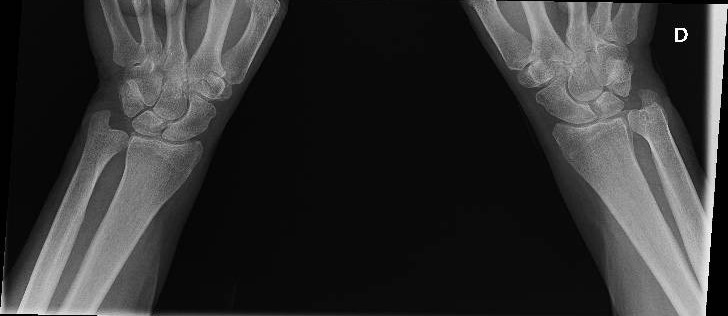

Radiografía de rodillas y manos: signos de condrocalcinosis.

Dada la falta de respuesta a la antibioterapia, se realizó una ecografía descartándose TVP. Ante la posibilidad de que el cuadro se tratara de un brote de artritis, se solicitaron cifras de ácido úrico que fueron normales, se realizó estudio de radiografía simple de rodillas y muñecas donde se evidenciaron datos de condrocalcinosis, haciendo probable el diagnóstico de enfermedad por depósito de pirofosfatos.